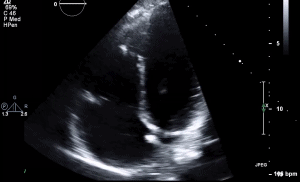

11 RVF A4C